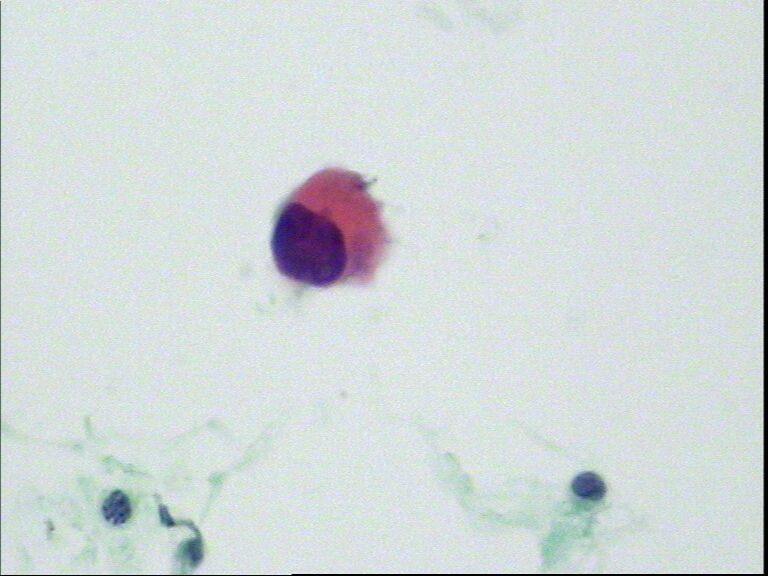

宫颈液基,老年妇女,78岁,临床:宫颈肥大

呵呵,最后三张就是普通的刮片

很漂亮的片子,赞一个。我考虑够报原位癌的了。